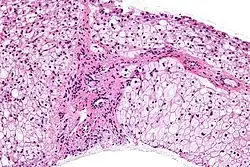

.jpg) | |

| Glycogen storage disease in hepatocytes | |